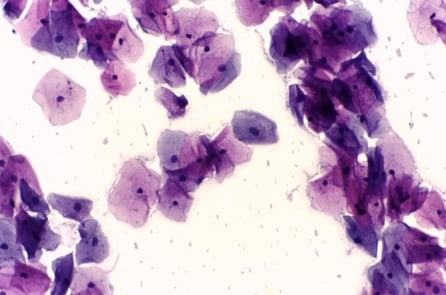

Pap smear (xét nghiệm Papanicolaou) từng là phương pháp sàng lọc ung thư cổ tử cung đã được sử dụng rộng rãi từ giữa thế kỷ XX. Tuy nhiên trong những năm gần đây, một số quốc gia bắt đầu từ bỏ dần vai trò của xét nghiệm này.

Sự thay đổi này xuất phát từ khác biệt về nguyên lý giữa hai phương pháp. Pap smear là xét nghiệm tế bào học, đánh giá hình thái tế bào tại thời điểm lấy mẫu. Kết quả phụ thuộc vào chất lượng lấy mẫu, kỹ thuật xử lý và khả năng đọc lame của nhân viên y tế. Dù Pap smear nhúng dịch (liquid-based cytology) đã cải thiện phần nào độ đồng đều của mẫu, xét nghiệm này vẫn cần nhiều nhân lực được đào tạo và thời gian xử lý.